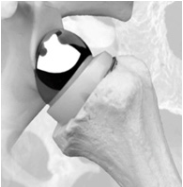

Omgekeerde schouderprothese

Wanneer de spieren (rotator cuff) rondom de schouder onherstelbaar versleten/gescheurd zijn, wordt een omgekeerde (reverse) schouderprothese gebruikt. Door de speciale vorm van de prothese wordt het draaipunt van het gewricht veranderd. Hierdoor kunt u andere spieren gebruiken om de arm op te tillen. Het schoudergewricht wordt met deze prothese eigenlijk omgedraaid. De schouderkop wordt vervangen door een kom met steel. De schouderkom wordt een kop door er een bol op te plaatsen.